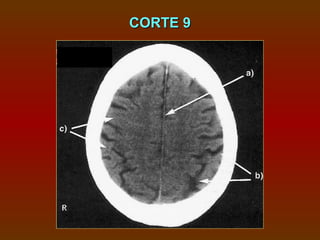

CORTE 9

a) Foice cerebral

b) Sulcos

c) Giros

CORTE 9 a) Foicecerebral b) Sulcos c) Giros